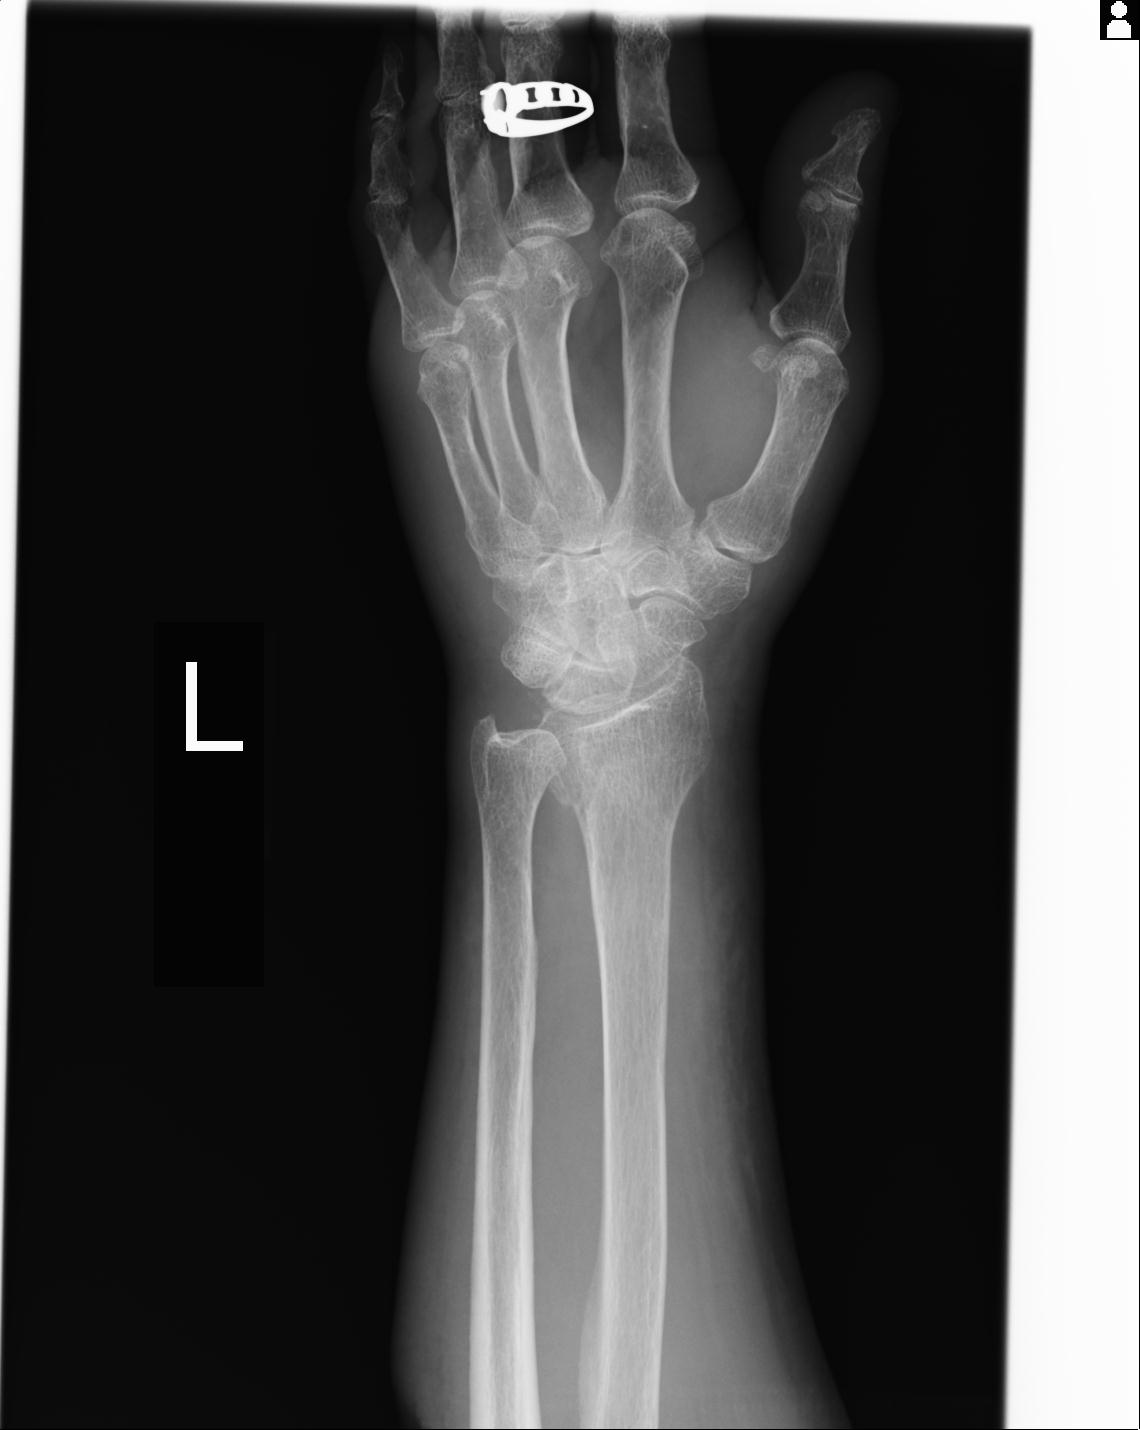

46666 1/23 両股正面+軸と右手関節 2R 76歳女性 右橈骨遠位端

46666 1/28 両股正面+軸と 1/26 右手関節 2R 76歳女性 右転子部骨折